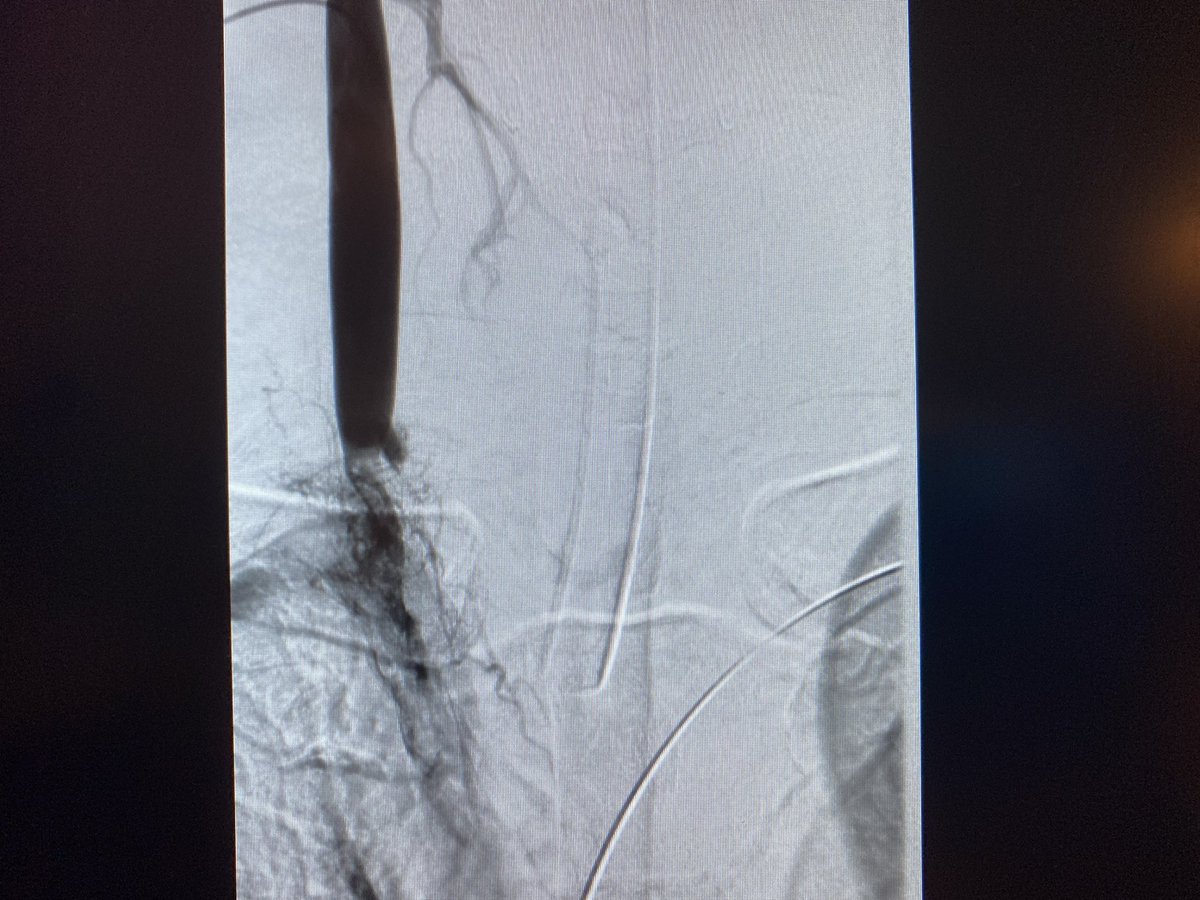

Central venous occlusion secondary to mesothelioma in a young patient with symptoms. R basilic, R CFV and RIJ access with the @InariMedical #ClotTrieverBOLD @anastasiah04 @CAIRweb